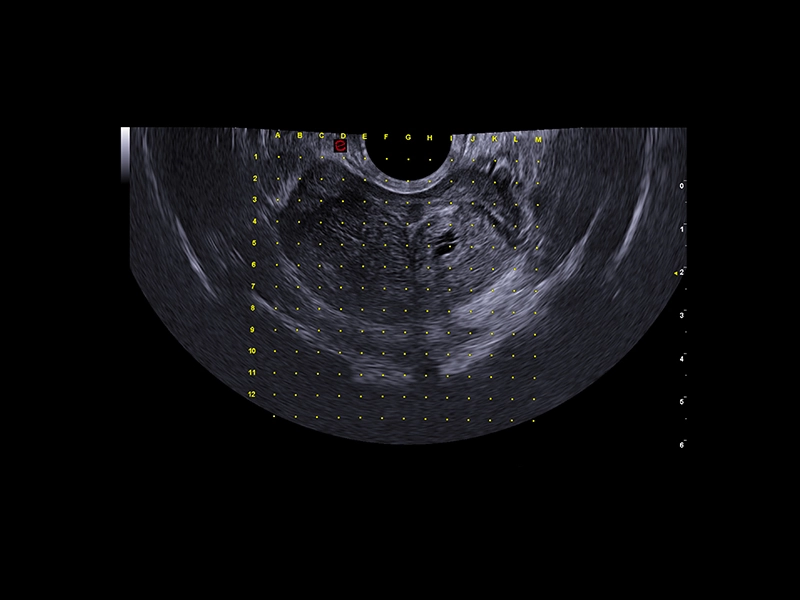

MyLab™E80 - Urofusion - Systematic Biopsy Guide

MyLab™E80 - Urofusion - Systematic Biopsy Guide